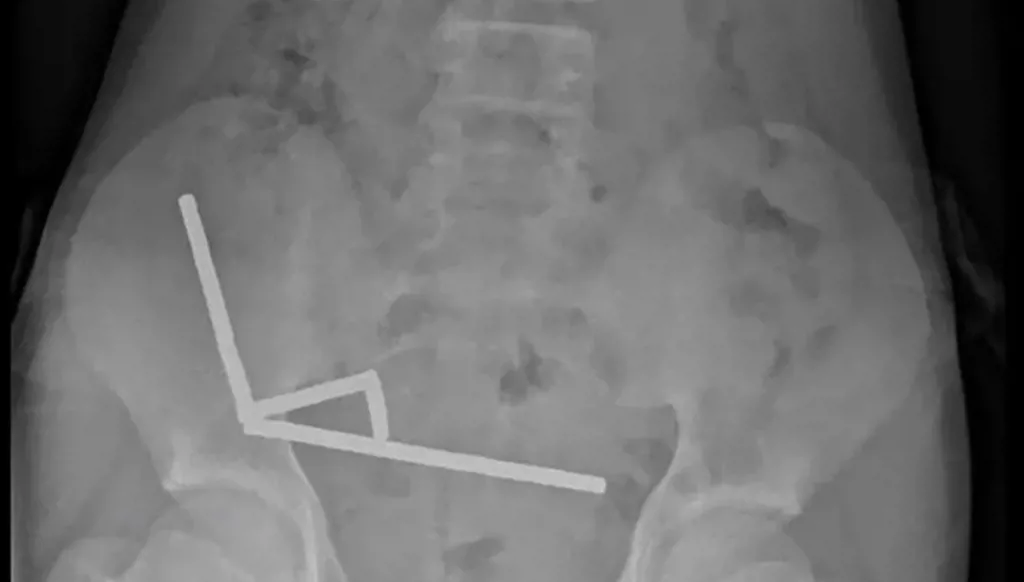

وأظهرت الأشعة أن المغناطيسات تكتلت معاً في 4 خطوط مستقيمة داخل أمعاء المراهق، و"يبدو أنها كانت في أجزاء منفصلة من الأمعاء ملتصقة ببعضها البعض بسبب القوى المغناطيسية"، وفق الأطباء.